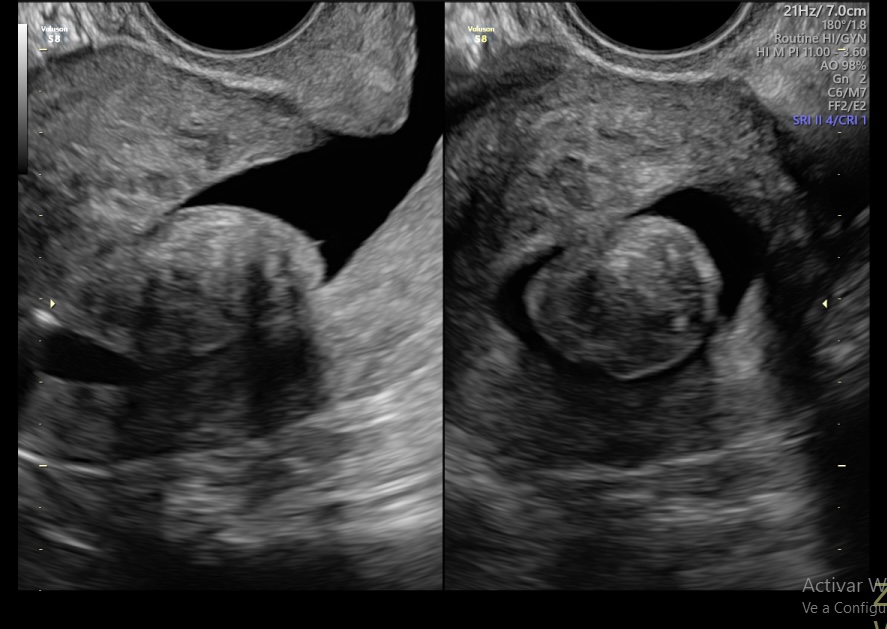

Ecografía Transvaginal

Estudio detallado de los órganos reproductivos femeninos (útero, ovarios, trompas) permitiendo diagnósticos precisos de miomas, quistes y otras condiciones pélvicas.